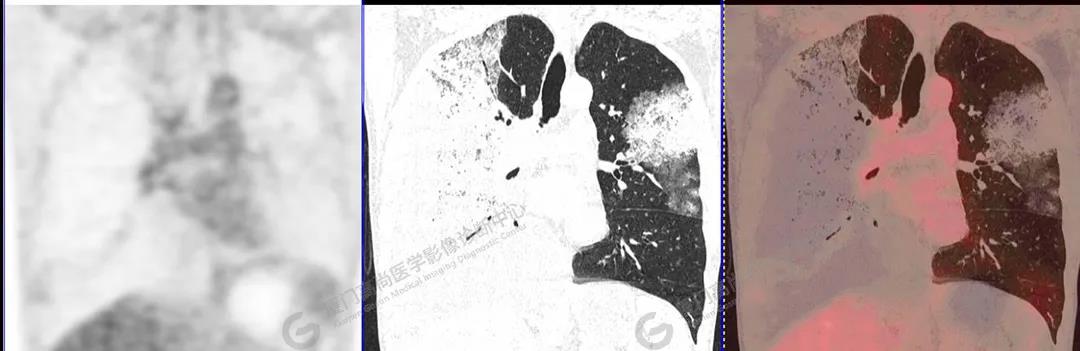

PET/CT影像圖

圖10

PET/CT所見(jiàn):雙肺大片實(shí)變影及磨玻璃影,部分呈地圖樣改變,累及右肺尖,部分放射性攝取輕微增高,SUVmax 1.77,其內(nèi)見(jiàn)多發(fā)支氣管充氣征象。

影像診斷: 雙肺大片實(shí)變影及磨玻璃影,大部分代謝不高,局部代謝輕微增高,考慮肺泡蛋白沉積癥,建議病理學(xué)檢查或肺泡灌洗物檢查。

影像學(xué)表現(xiàn):HRCT上雙肺斑片影,以肺門(mén)為中心呈蝶翼狀對(duì)稱(chēng)分布;病變可隨機(jī)分布在中央?yún)^(qū)、周?chē)鷧^(qū)或全肺葉,病灶與正常分組織分界清楚,呈典型“地圖樣”改變;有支氣管充氣征,但表現(xiàn)為充氣支氣管細(xì)小且數(shù)量及分布稀少;“碎石路”征由彌漫性磨玻璃影及內(nèi)部網(wǎng)格樣小葉間隔增厚組成(鋪路石樣表現(xiàn))。無(wú)空洞、蜂窩狀改變、淋巴結(jié)腫大、胸腔積液及明顯實(shí)變等。肺內(nèi)病灶累及范圍、磨玻璃密度高低與PAP患者的病情嚴(yán)重程度相關(guān),嚴(yán)重者病灶累及全肺,同時(shí)出現(xiàn)肺內(nèi)大片實(shí)變,并見(jiàn)充氣支氣管征象。PAP影像學(xué)表現(xiàn)程度與臨床癥狀、體征嚴(yán)重程度不成比例,表現(xiàn)為影像改變重,臨床癥狀輕。